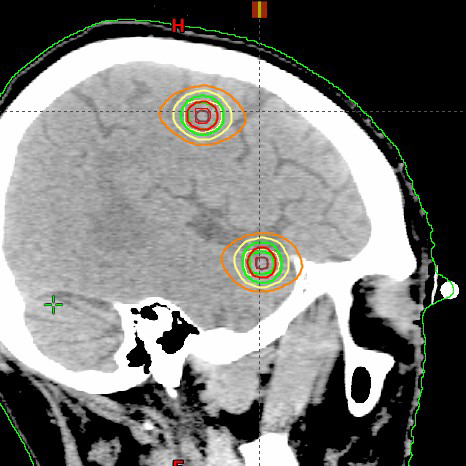

肺癌脳転移(2カ所),20Gy/1回 患者さんの感想:こんなに安心して治療が受けられるとは驚きでした。 武田先生の落ち着いた自信あふれる安心対応にホッとしました。看護師の皆様の気遣い、やさしい対応で、技師の皆様の自信に満ちた対応でした・・・(つづきを読む) |